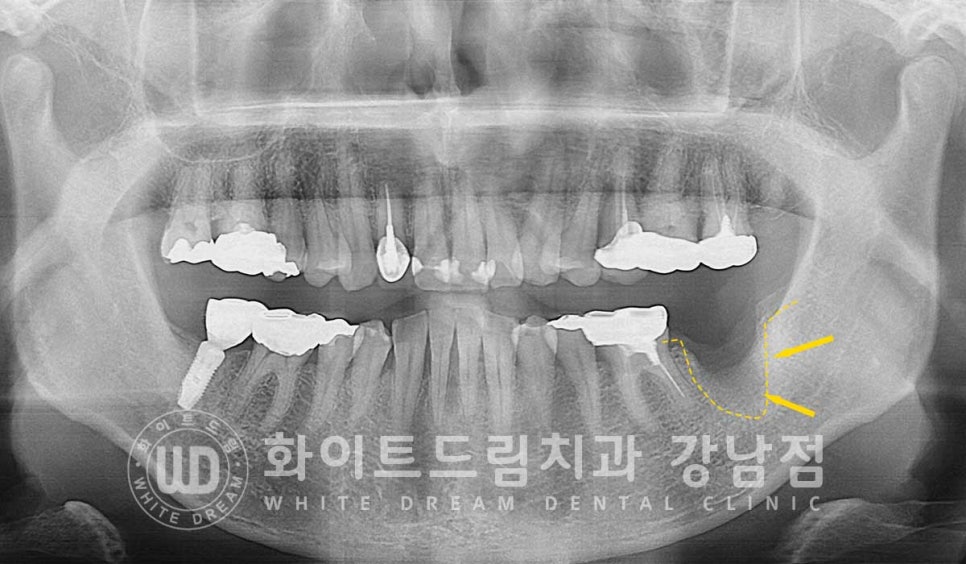

환자분은 2개월 정도 잇몸뼈의 회복을 지켜본 후

소실된 잇몸뼈를 생성하기 위한 뼈이식과 임플란트를 식립했습니다.

오스 soi 임플란트 5.0x8.5mm 식립 후 모습니다.

(강남역 임플란트재수술 치과 / 수술일자 : 23.10.26)

이식재가 새로운 뼈로 잘 생성되면서 임플란트와 단단하게 굳기를

기다리는 시간이 또 필요합니다.